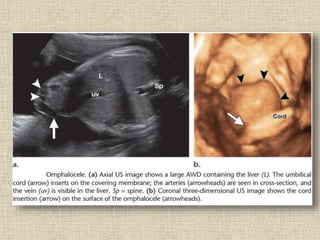

Omphalocele

Omphalocele refers to herniation of the intestine and other abdominal

organs into the base of the umbilical cord through an enlarged umbilical

ring, with the umbilical cord inserting at the apex of the herniated sac. The

herniated content is covered by amnion and peritoneum.

Prenatal Diagnosis

• In the first trimester, physiologic midgut herniation can be mistaken for

an omphalocele. It should resolve by 12 weeks.

• It should never include the liver, and the herniation should not be more

than 1 cm into the cord.

• The presence of even small herniation into the base of the umbilical

cord beyond 12 weeks is therefore diagnostic of omphalocele.

• In cases of large defects, the omphalocele may contain other organs

such as liver and stomach.

• The umbilical cord can be seen inserted on the herniated sac rather than

directly to the abdominal wall.